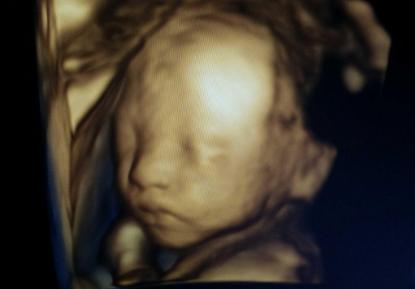

四维彩超是一种检查可能存在唐氏综合征的技术,它可以在胎儿的发育过程中检测出唐氏综合征的潜在症状。四维彩超是一种四维技术,它可以拍摄出胎儿的多个视图,从而让医生更好地分析和识别胎儿的症状。由于它可以有效地检测出潜在的唐氏综合征症状,因此它受到了越来越多的育儿者的青睐。

四维彩超检查可以检测出可能存在唐氏综合征的潜在症状,但无法完全排除唐氏综合征的可能性,因此孕妇在发现胎儿可能有唐氏综合征症状时,应尽早进行四维彩超检查,并在检查后进行其他检查,以确定胎儿是否患有唐氏综合征。四维彩超检查对于确定唐氏综合征的重要性,不言而喻,但也要注意,它不能完全排除唐氏综合征,只有结合其他检查,才能正确诊断唐氏综合征。

小提示:总的来说尽管四维彩超可以在胎儿发育过程中检测出可能存在的唐氏综合征的潜在症状,但它并不能完全排除唐氏综合征,只有通过进一步的检查,如血液检查、基因检测等,才能比较终确定胎儿是否患有唐氏综合征。因此建议孕妇在发现胎儿可能存在潜在唐氏综合征症状时,应及早进行四维彩超检查,并在检查后进行其他检查,以确定胎儿是否患有唐氏综合征。